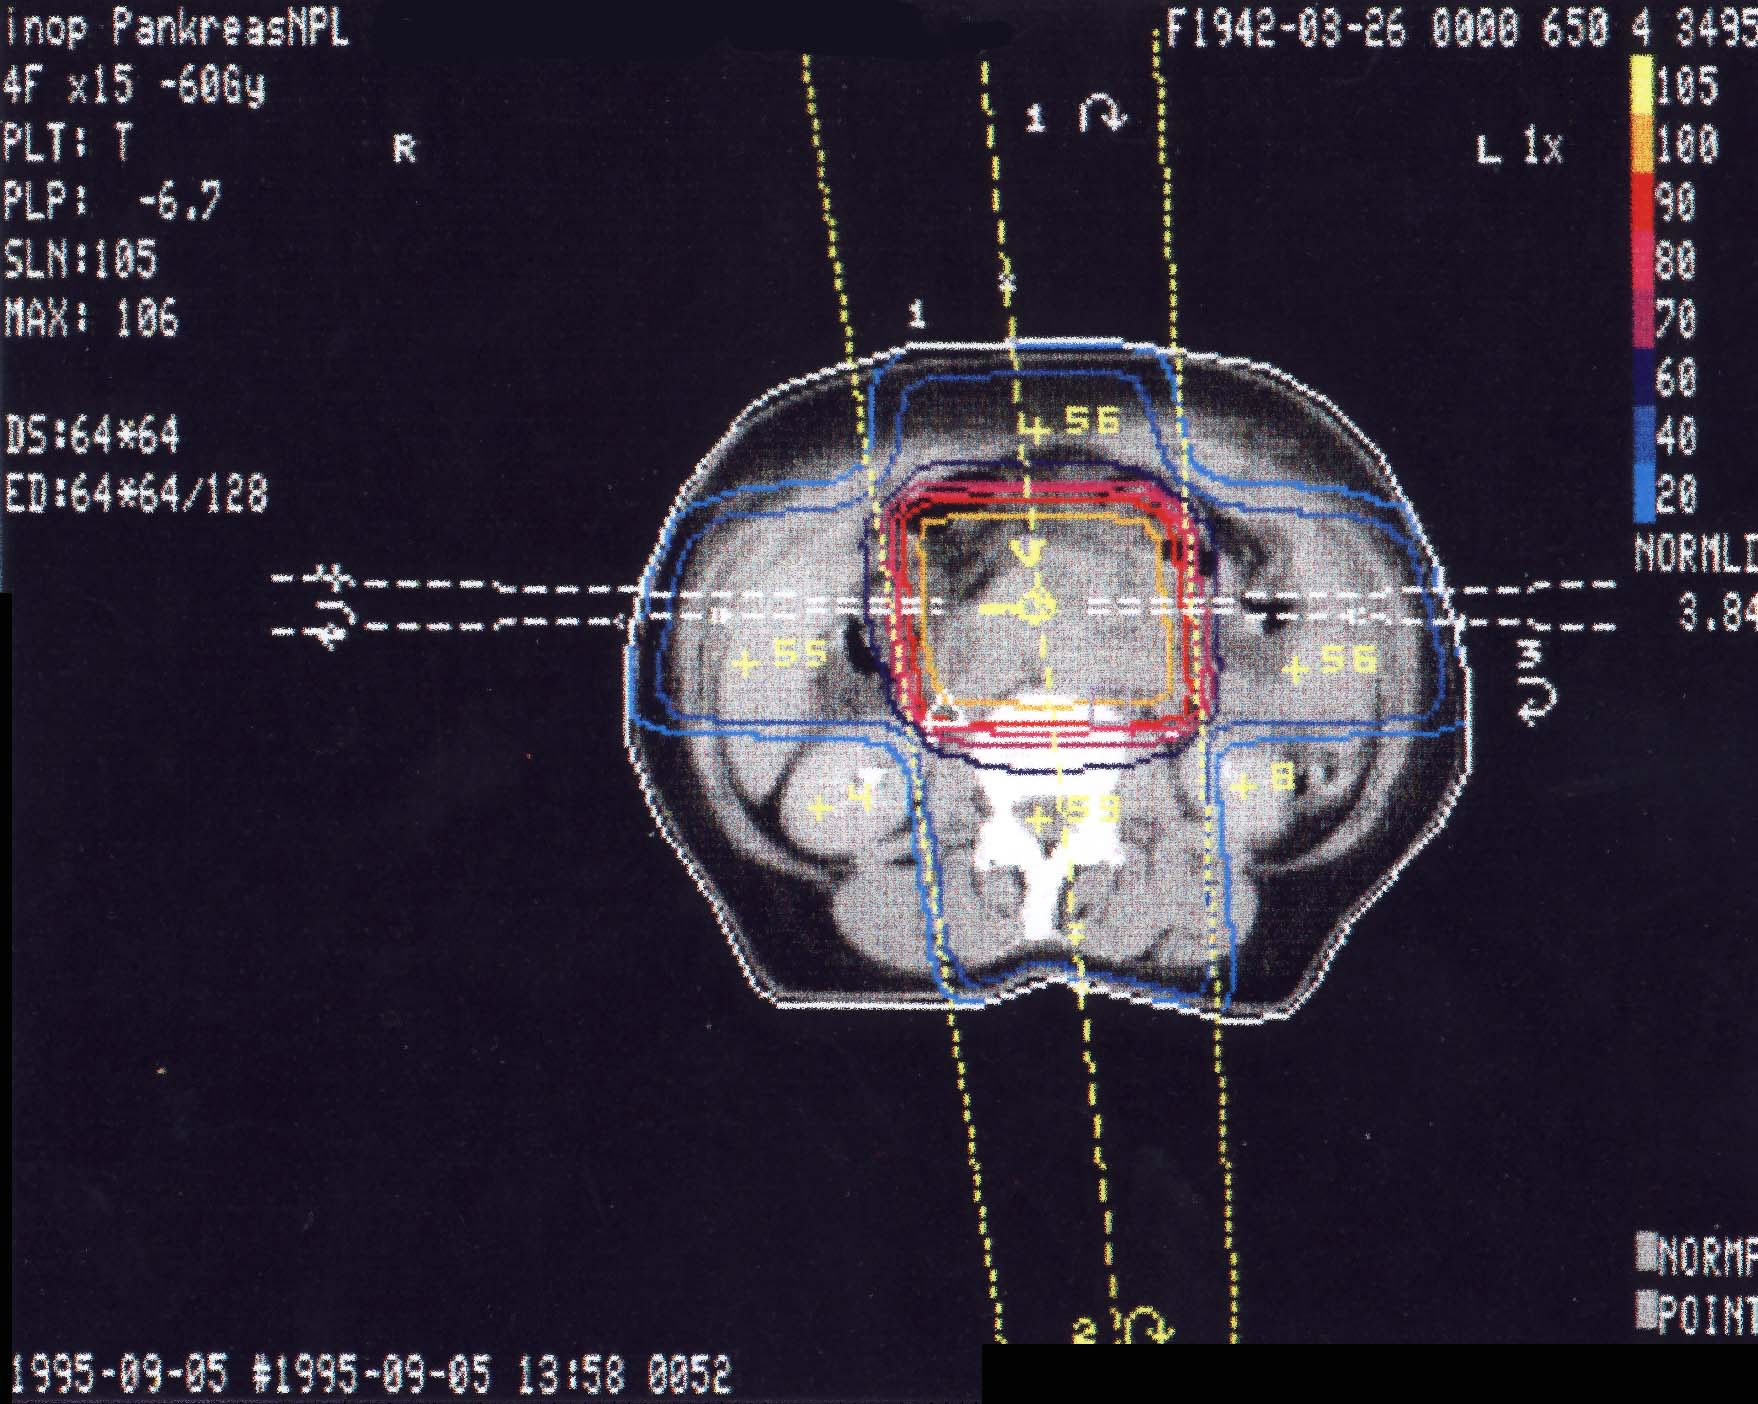

Tumore der Bauchspeicheldrüse (Pankreas): Bestrahlungsplan

Einführung aktuelle Bilder - Einführung Bestrahlungspläne - Einführung Demonstration